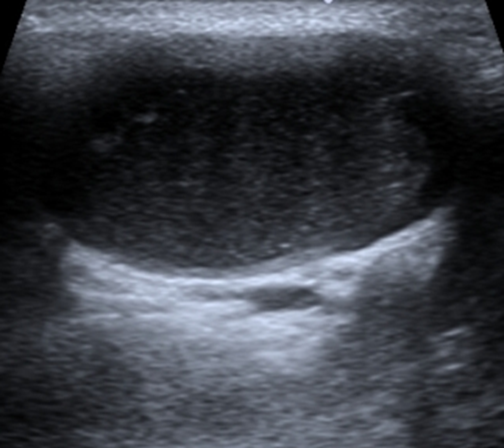

• Ultrasound: Commonly used as an initial imaging technique to distinguish cystic masses from solid masses. It shows a well-defined, anechoic (fluid-filled) structure with regular borders.